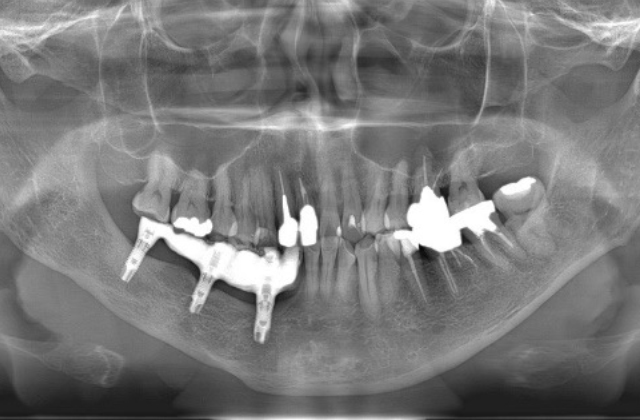

当科では、口腔内や顎骨内に発生する良性腫瘍、嚢胞性疾患に対し手術を行っています。ともに無痛性に緩慢な増大を特徴とするため、発見された際には顎骨の広範囲におよび、歯根吸収や下顎管の圧排を伴っている症例も少なくありません。特に若年者の顎骨腫瘍(嚢胞)の場合、顔貌の変形や下歯槽神経の損傷に配慮し、まず初期治療として開窓を行い、病変の縮小と骨新生を確認後に摘出を行います。ただし、エナメル上皮腫などの再発率の高い病変に対しては、一期的に顎骨切除を行うとともに、腸骨や腓骨を用いた硬組織再建を積極的に行っています。その際は術前にCT撮影を行い、3D画像によるモデルサージェリーを基にオーダーメイドのプレートを作製し、確実かつ迅速な手術を行っております。